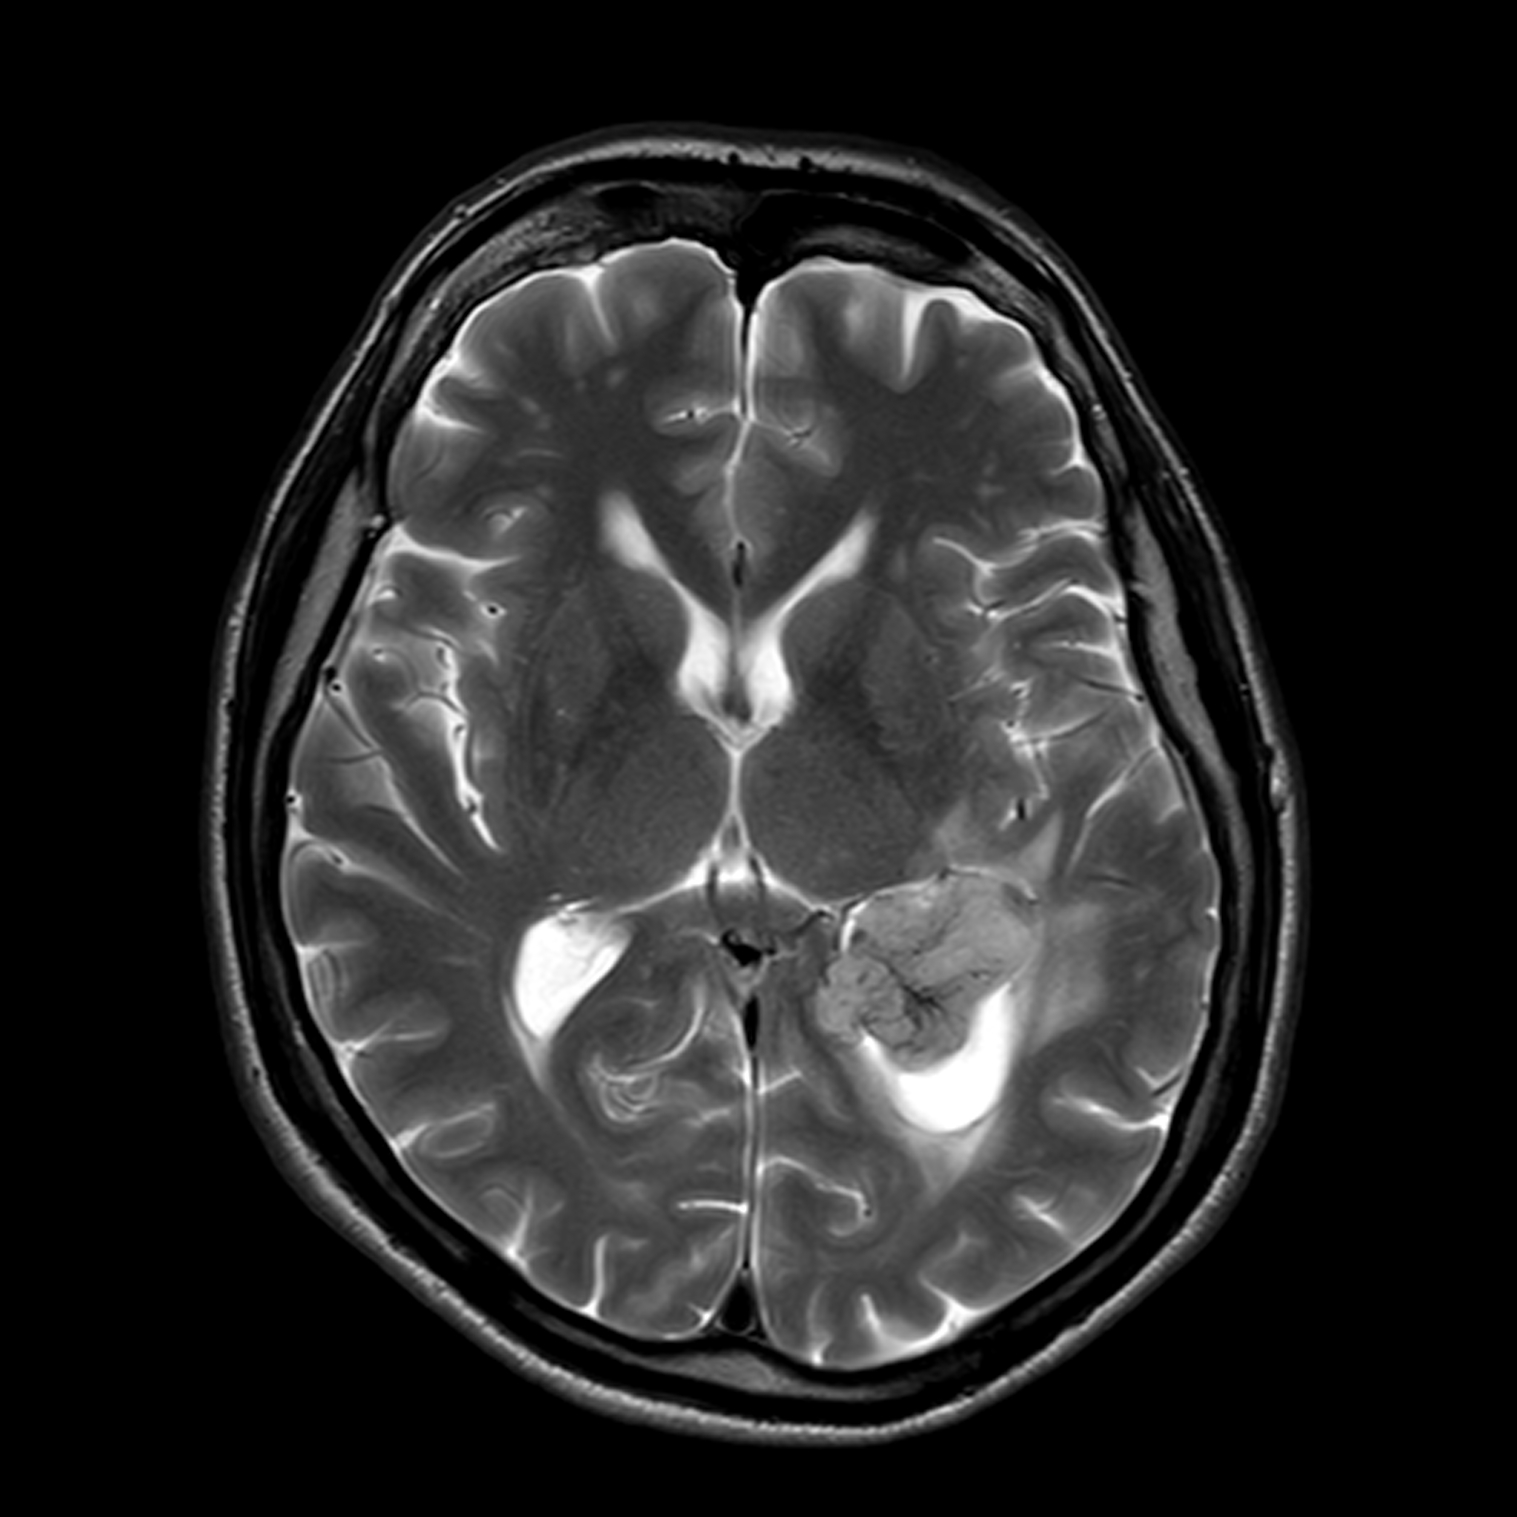

МРТ головного мозга: показания и результаты

Раздел: Визуальный дайджест